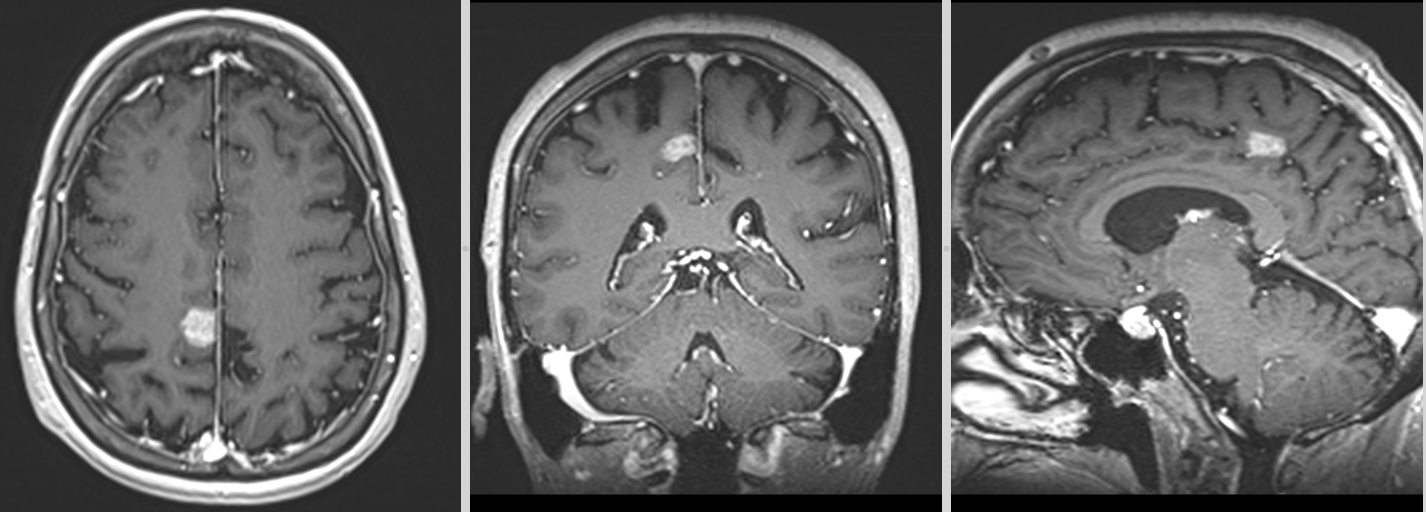

- Imagistică cerebrală: RMN-ul cu substanță de contrast este metoda de elecție, dar și CT-ul poate fi util.

Metastazele cerebrale apar frecvent în emisferele cerebrale (80%), mai rar la nivelul cerebelului (15%) sau trunchiului cerebral (5%). Localizarea influențează simptomele și posibilitățile de tratament.

Celulele canceroase se desprind din tumora primară, pătrund în vasele de sânge și călătoresc spre creier. Acolo, ele trec de bariera hemato-encefalică – o structură protectoare care apără creierul de substanțe toxice – și încep să se multiplice. De cele mai multe ori, metastazele apar în zona joncțiunii dintre substanța albă și cea cenușie, unde fluxul sanguin este bogat și viteza de circulație este mai redusă.